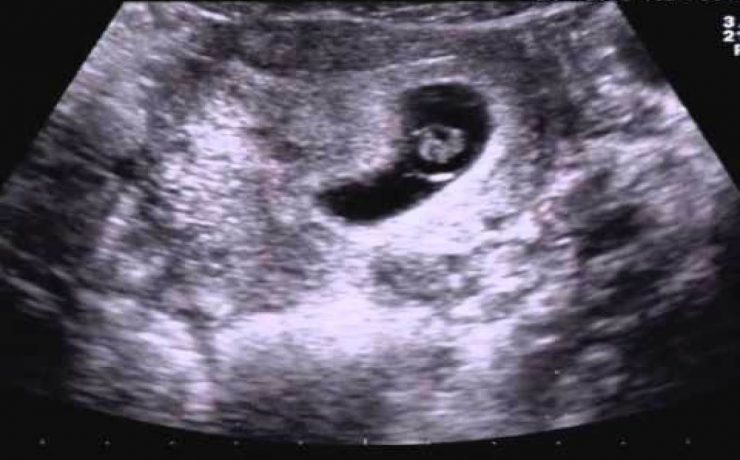

Introducción: El cáncer de endometrio es la segunda neoplasia ginecológica a nivel mundial ,más común en la perimenopausia , la incidencia es de 6 veces mayor en países desarrollados que en los menos desarrollados. La supervivencia en etapas tempranas es del 80%. Estudios de tamizaje Escrutinio a partir de los